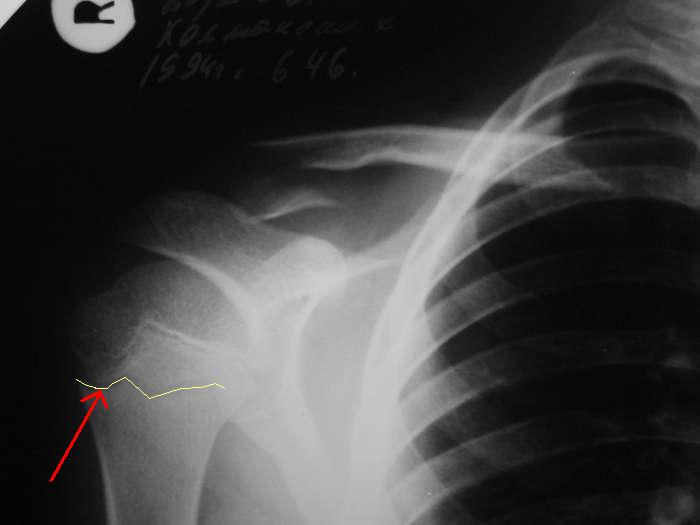

Re: Перелом ключицы

Александр, простите за настойчивость, на картинке я указал смутившую меня тень ... это вариант зоны роста?